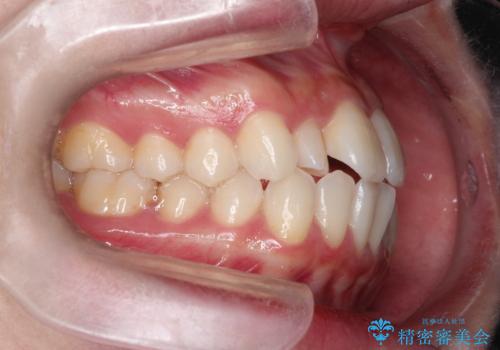

- 口元をさげたいという主訴で来院されました。4番の歯を4本抜歯し、遠心移動とIPRをしました。右上2番が矮小歯のため見た目を重視するならクラウンの提案をしましたが、そのままでの治療を希望されました。

矯正治療の最終段階でスペースクローズにやや時間がかかりましたが、前歯が下がったことで口元の位置も下がりきれいになりました。